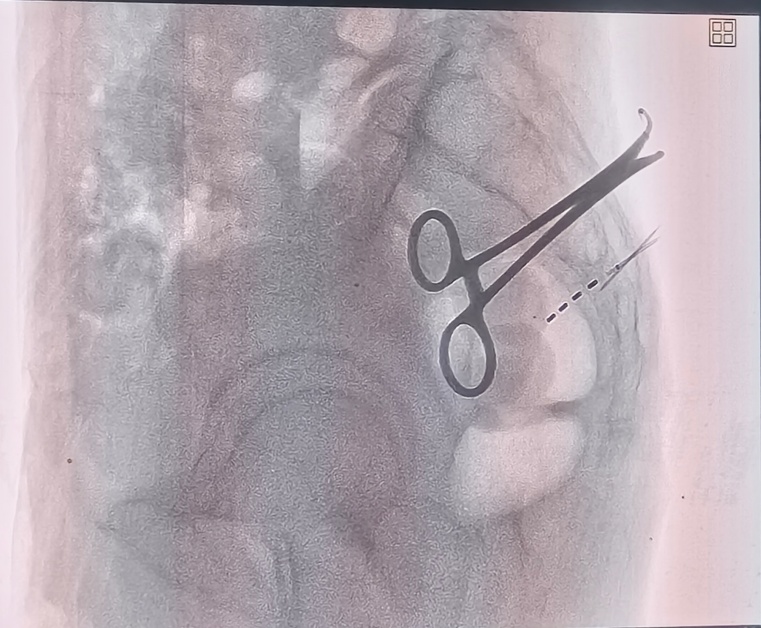

考虑到李爷爷高龄、病情复杂,郑学胜团队量身定制了骶神经调节术方案。该手术通过微创方式植入电极,精准调节骶神经功能,恢复肠道正常蠕动节律。

骶神经电极植入